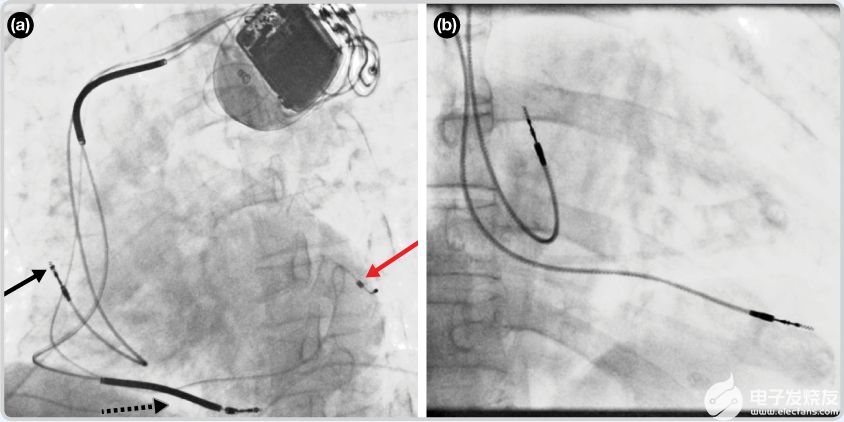

CRT设备如图4(a)的透视图像所示。这是医生用来放置引线的图像。这样的形象对于外行人来说很难解释。你可以看到心脏的浅色轮廓——跳动的心脏的静态视图。它位于右心房,心脏的顶点指向右侧和向下。在这个典型的引线放置中,黑色箭头指向右心房引线。黑色虚线箭头指向右心室导联线。部分可见的导联线(由红色箭头表示)是左心室导联线(红色箭头指向电极尖端)。图4(b)显示了双腔起搏器典型导联放置的透视图像。右心房导联线朝上,放置在右心房。右心室导联线位于右心室的顶点。

图4.透视图像显示起搏器导线放置。3(a). 单腔起搏器。(b). 双腔起搏器。